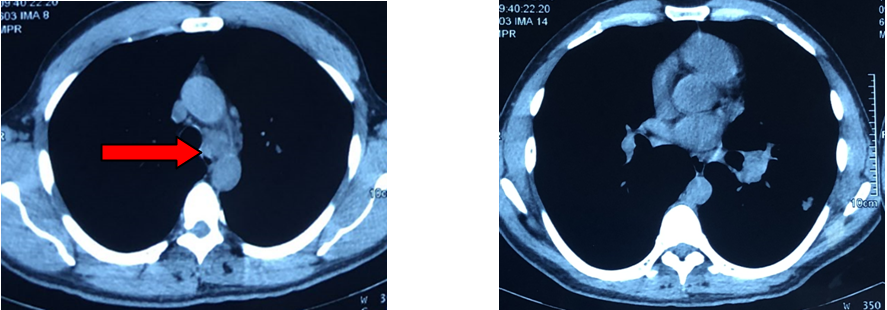

- Hình ảnh chụp cắt lớp vi tính lồng ngực sau điều trị 5 tháng (hình 3a, 3b):

Khối u thùy dưới phổi trái với kích thước 1,8x1,5cm

Không thấy hạch trung thất và hạch rốn phổi.

Không thấy nốt tổn thương thứ phát phổi phải.

Hình 3a: Hình ảnh chụp cắt lớp vi tính lồng ngực cho thấy khối u thùy dưới phổi trái với kích thước 1,8x1,5cm (vòng tròn vàng). Không thấy nốt tổn thương thứ phát phổi phải.

Hình 3b: Hình ảnh chụp cắt lớp vi tính lồng ngực không thấy hạch trung thất và hạch rốn phổi.